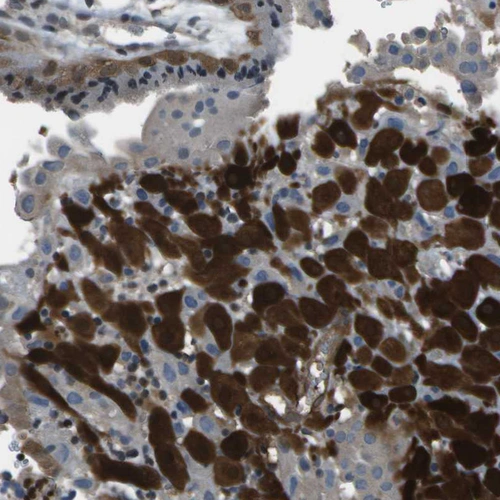

Immunohistochemical staining of human Heart muscle shows moderate cytoplasmic positivity in cardiomyocytes.